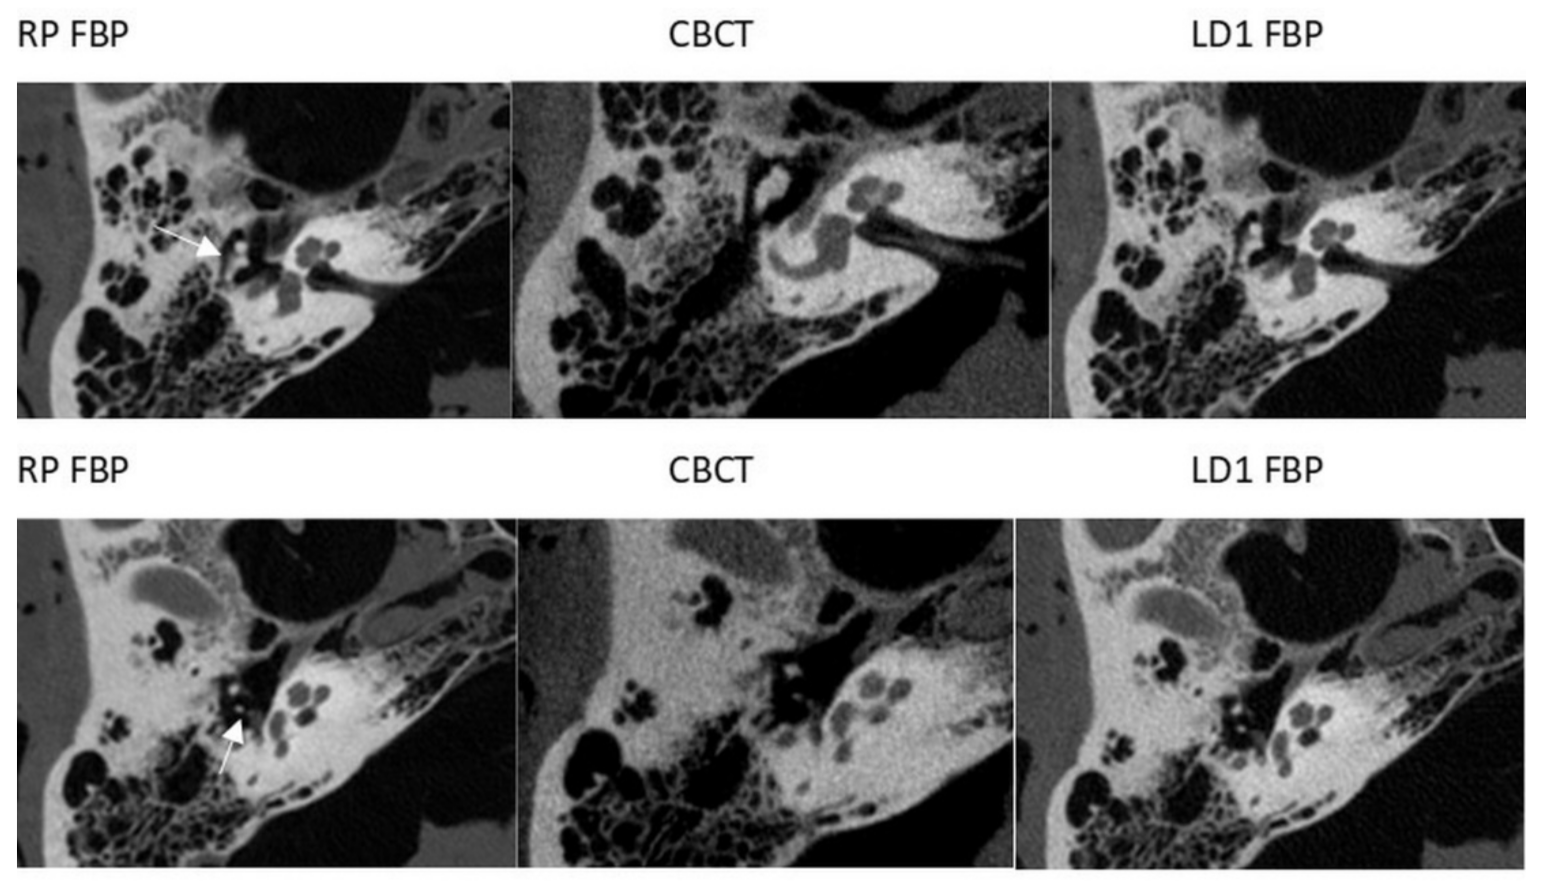

3.1. CT

3.2. CBCT